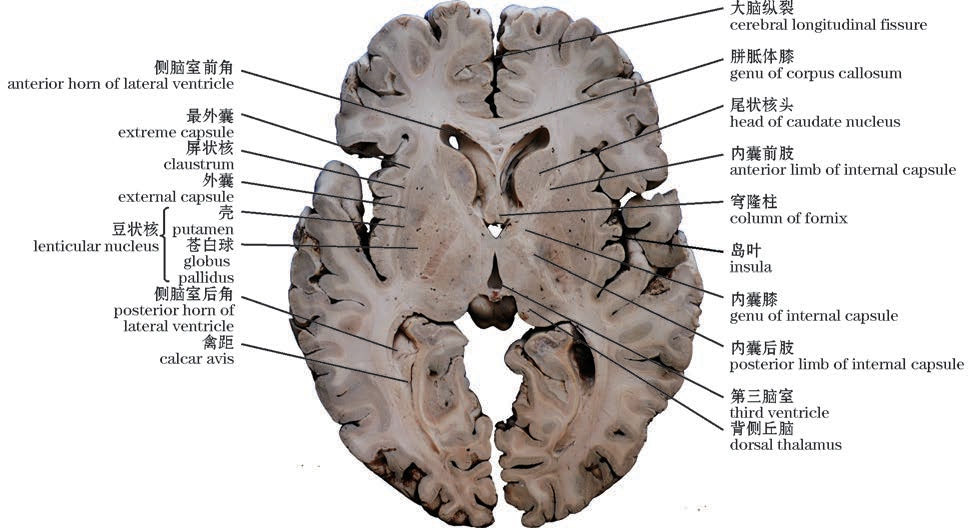

img

图10-13 脑的水平切面(经内囊)